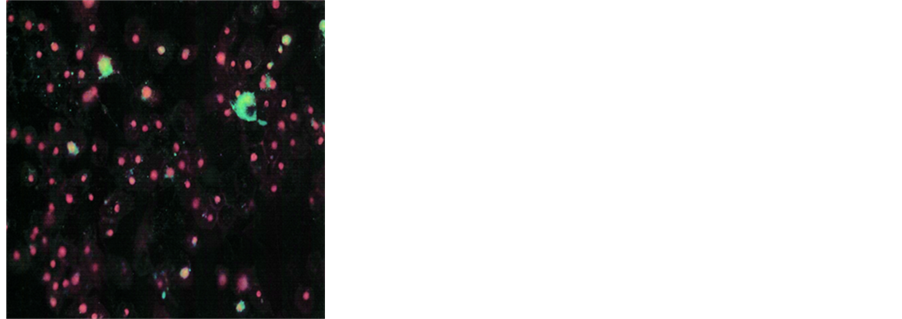

3.2. Nutrient Mixture Induced Apoptosis through Induction of Caspases

Quantitative analysis of DU-145 cells in early and late apoptotic stages was done by using the Live Green Caspase assay. Analysis with Live Green Caspase detection kit revealed a dose dependent increase in apoptosis of DU-145 cells with slight apoptosis found at 100 μg/ml, moderate at 500 μg/ml and significant at 1000 μg/ml

NM. Quantitative analysis of the data revealed the percentage of apoptotic cells to be 6% at 100 μg/ml (all in early phase apoptosis), 49% at 500 μg/ml (10% in early phase; 39% in late phase) and 83% for 1000 μg/ml NM (8% in early phase; 75% in late phase). It was observed that there was a corresponding decrease in percentage of live cells and an increase in percentage of cells in late apoptotic stages with increasing NM concentrations. A quantitative analysis of apoptosis induction in normal human dermal fibroblasts showed equivalency to DU-145 cells at 100 μg/ml. However, at higher concentrations of NM the induction of apoptosis was significantly lower in NHDF cells as compared to DU-145 cells. The percentage of apoptotic NHDF cells was 7% at 100 μg/ml (2% in early phase, 5% in late phase), 25.6% at 500 μg/ml (4.6% in early phase, 21% in late phase) and 76.5% at 1000 μg/ml (23.5% in early phase, 53% in late phase). Photomicrographs of apoptotic DU-145 cells and NHDF are shown in Figures 2(a)-(d) and Figures 3(a)-(d), respectively. The quantitative analysis of live, early and late DU-145 prostate cancer cells and NHDF cells are shown in Figure 2(e) and Figure 3(e), respectively.

Figure 2. Effect of NM on induction of apoptosis in prostate cancer DU-145 cells. Photomicrographs of DU-145 cells (×20 magnification) treated with (a) 0 mg/ml, (b) 100 mg/ml, (c) 500 mg/ml, (d) 1000 mg/ml concentrations of NM respectively. (e) Analytical representation of the differential distribution of cells in early or late phases of apoptosis upon treatment with 0, 100, 500 and 1000 mg/ml NM concentrations.